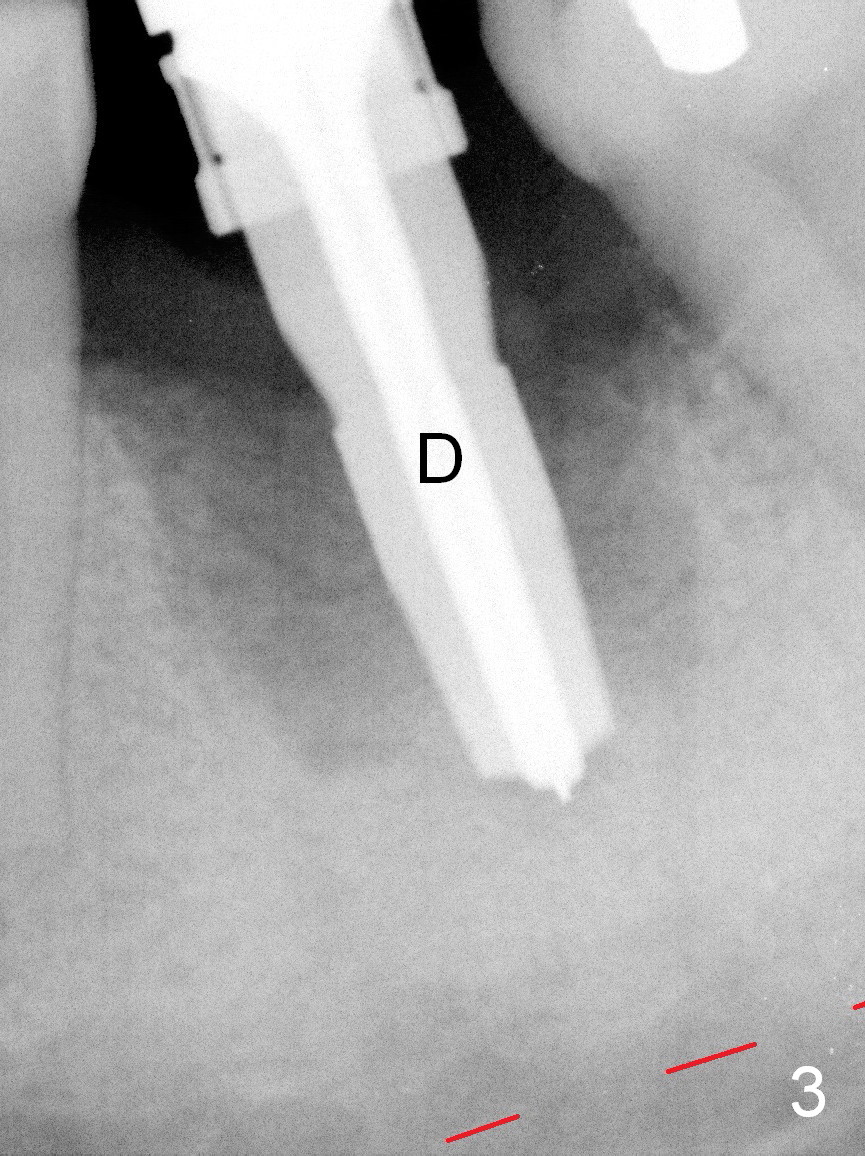

A 37-year-old lady (MP) presents to clinic with chief complaint of bad smell from lower right crown (Fig.1: #19; red dashed line: superior border of the Inferior Alveolar Canal). One of the most prominent pathologies is fracture of the distal root (<). After extraction, the socket is treated with 2% Xylocaine/1:50,000 Epinephrine. The coronal distobuccal plate is defective. Osteotomy is initiated as lingual as possible. The 1st intraop PA shows that the osteotomy is shallow and distal to the almost non-existent septum (Fig.2 S). The osteotomy is intended to move more mesially, but the result is not obvious when 4.5x14 mm drill is in place (Fig.3 D). The depth of the osteotomy is increased by 3 mm; a 5x17 mm tap is stable (Fig.4 T). A 5x12 mm implant (Fig.5 I) is placed until it cannot be turned. The implant is higher than the distal crest (^). In addition there is space apical to the implant (Fig.5*). After 5 mm drill is used, the implant is seated deeper with insertion torque < 35 Ncm (Fig.6). It suggests overprep. Anyway, an immediate provisional is fabricated after placement of an abutment (A). After reline, the provisional fits well. It has to be removed with forceps for occlusal adjustment. Finally the abutment/implant complex turns in the socket with fingers. The rotation/position of the complex is randomly adjusted. When the provisional is cemented, it does not seat completely, but is stable. If the implant osteointegrates, the provisional must play a role in stabilizing the implant. Bone graft is placed in the gap prior to cementation (Fig.6 *).